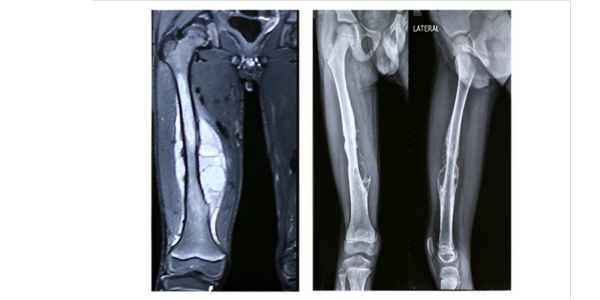

A male patient of 7-year-old hailing from Mumbai, Maharashtra, a student, was diagnosed with Periosteal Ewing`s Sarcoma of Right femur. Patient underwent Neoadjuvant Chemotherapy as part of treatment protocol.

After 9 cycles of NAC, shrinkage of soft tissue mass and bone edema was noted. There was resolution of periosteal reaction as well, all pointing to a favorable response to chemotherapy.